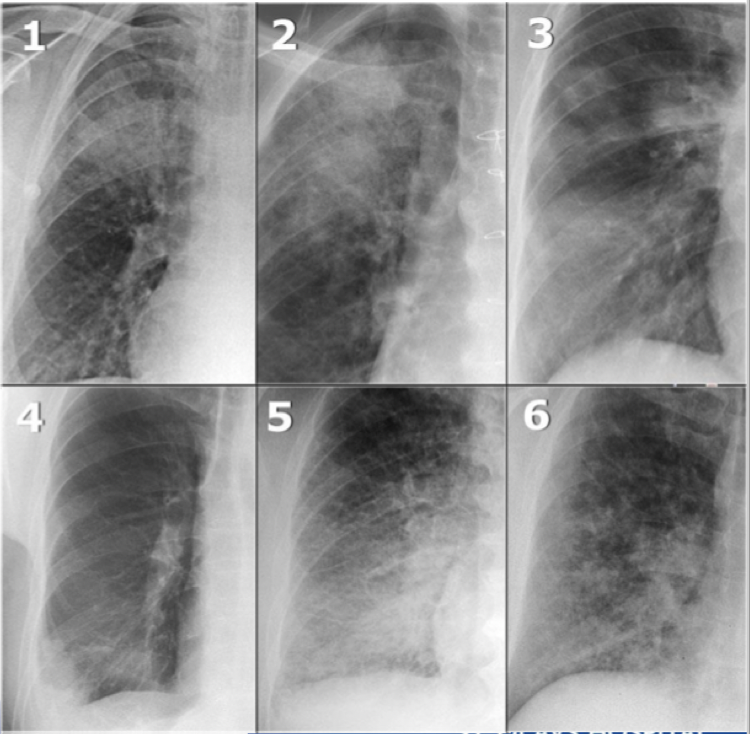

Hva er viktigst når det gjelder konsolidering?

Klinikken er viktigst

Eks. på konsolidering: 1. Pneumoni 2. Blødning 3. Organiserende pneumoni 4. Lungeinfarkt 5. Lungeødem 6. Sarkoidose